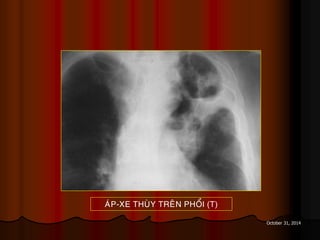

AÙP-XE THUØY TREÂN PHOÅI (T)

October 31, 2014 AÙP-XETHUØY TREÂN PHOÅI (T)